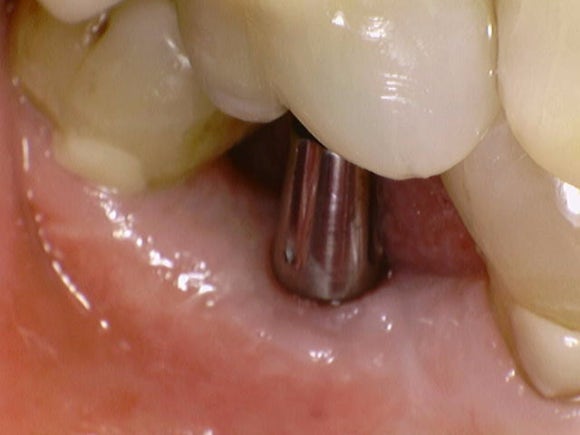

20250328

2개월이 흘러, 이제 머리를 세울 시간이 되었습니다.

임플란트 뿌리에 기둥을 연결합니다.